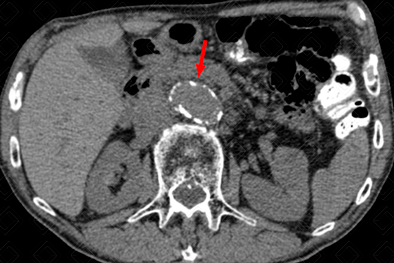

Texto alternativo para a imagem Figura 2. Créditos: Dra. Elazir Mota - Rio de Janeiro/RJ

Descrição das figuras 1, 2 e 3: Sinais de ruptura de aneurisma da aorta abdominal com extenso hemoperitônio. Hematoma hiperdenso mais bem apreciado nas fases sem contraste (asteriscos - figuras 1 e 2), que se estende ao espaço pararrenal e perirrenal esquerdo. Após a administração do contraste, observa-se extravasamento ativo do mesmo (seta vermelha - figura 3). [cms-watermark]